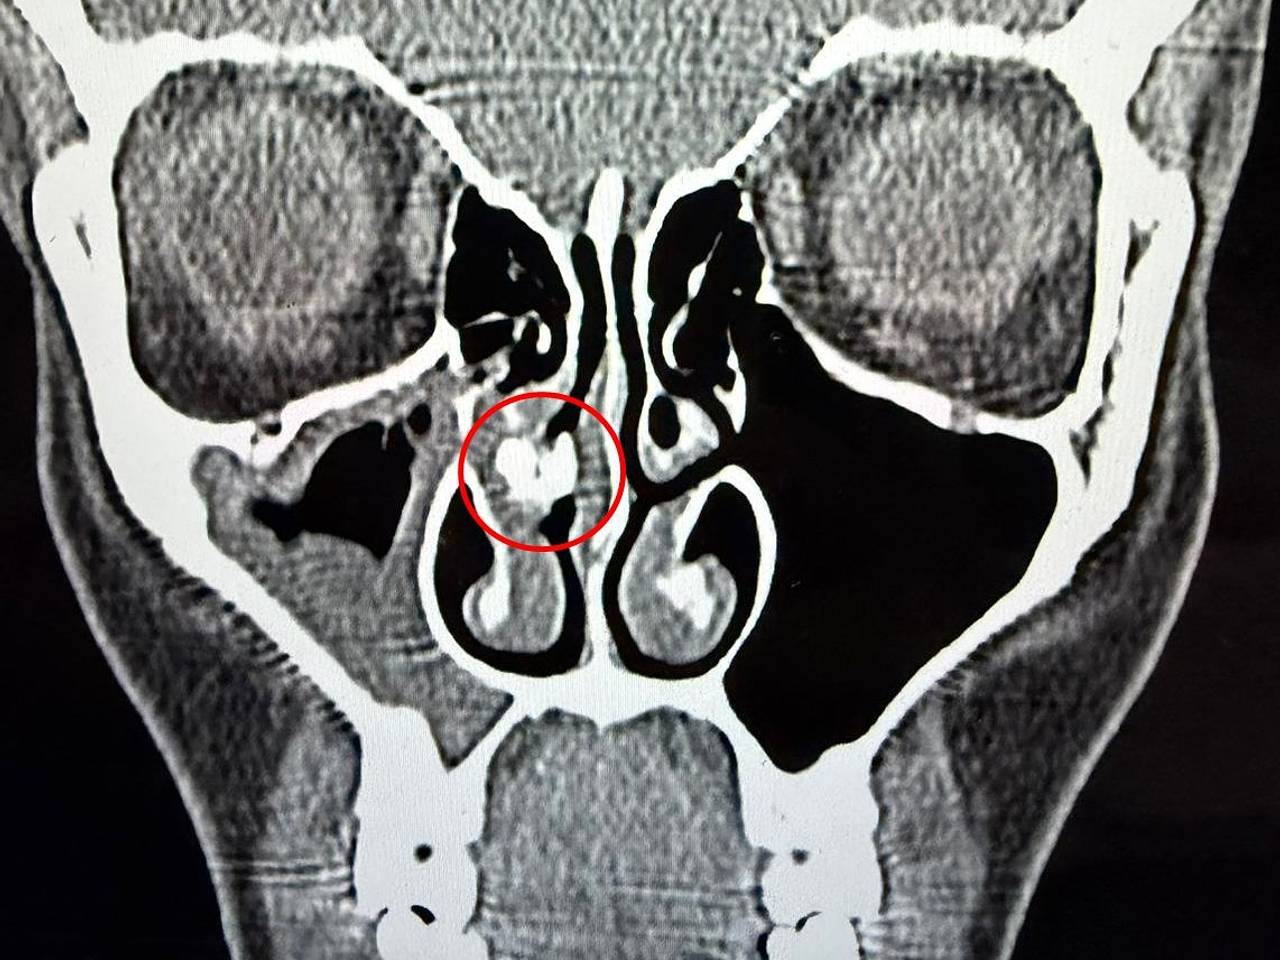

Ситуация изменилась в 2025 году, когда Рейбо обратилась в больницу с синуситом — воспалением слизистой оболочки носовых пазух. Врачи провели компьютерную томографию и обнаружили в одной из ее ноздрей инородное тело.

Спустя час его удалось удалить с помощью пинцета, и оказалось, что это был кусок скотча. Рейбо опубликовала видео с находкой в TikTok и призналась, что не знает, как именно клейкая лента попала в ее нос.